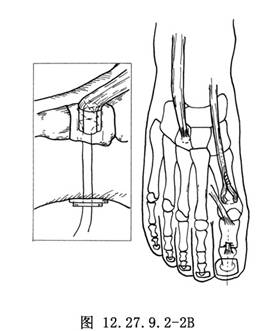

10.1 1.Jones手术(𧿹长伸肌腱后移及趾间关节融合)

做“L”形切口显露𧿹趾趾间关节(图1a),将皮肤和皮下组织瓣向内、向近侧拉开,找到𧿹长伸肌腱。在趾间关节近侧1cm处横断肌腱,去除趾间关节面软骨,用一根直径为0.2cm的斯氏钉或两根直径为0.16cm的克氏针逆行固定,于皮下剪断内固定针。另做一个2.5cm长的足背内侧切口显露第1跖骨颈(图12.27.9.2-1A),注意保护𧿹短伸肌腱,并沿切口全长切开其腱鞘。在第1跖骨颈部位由跖内侧到外侧横向钻孔,将肌腱经孔穿过,调整合适张力后与自身做间断缝合(图12.27.9.2-1B)。